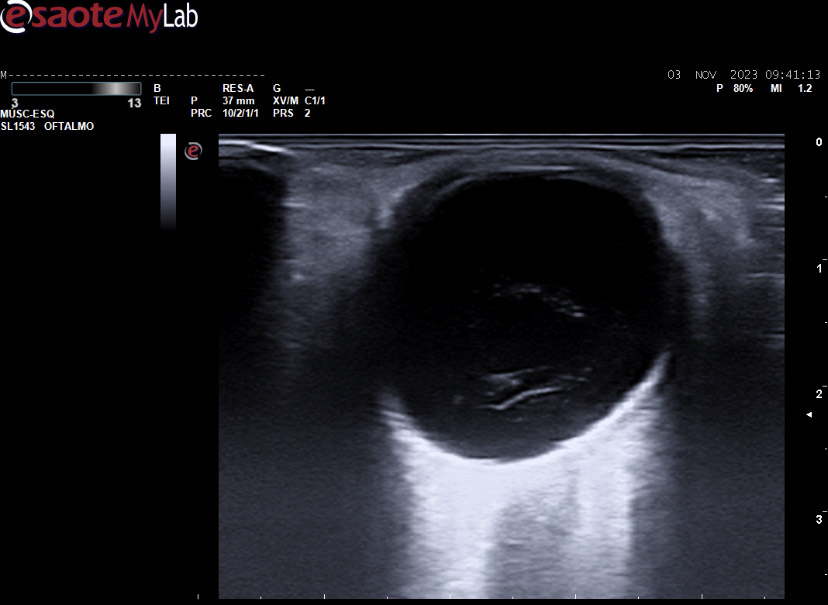

Ecografía ocular: lesión sólida polipoidea homogénea de 10*6 mm vascularizada junto a imagen de membranas hiperecoicas avasculares y móviles con los movimientos oculares en polo posterior.

Se deriva a urgencias oftálmicas hospitalarias donde corroboran nuestras imágenes con otra ecografía realizada por servicio de radiodiagnóstico y completan estudio con RMN: lesión coroidea hiperintensa en T1 e hipointensa en T2 de medidas basales de 16 mm por espesor de 6 mm con desprendimiento de retina posteroinferior y pequeño foco de hemorragia subretiniana posterior.